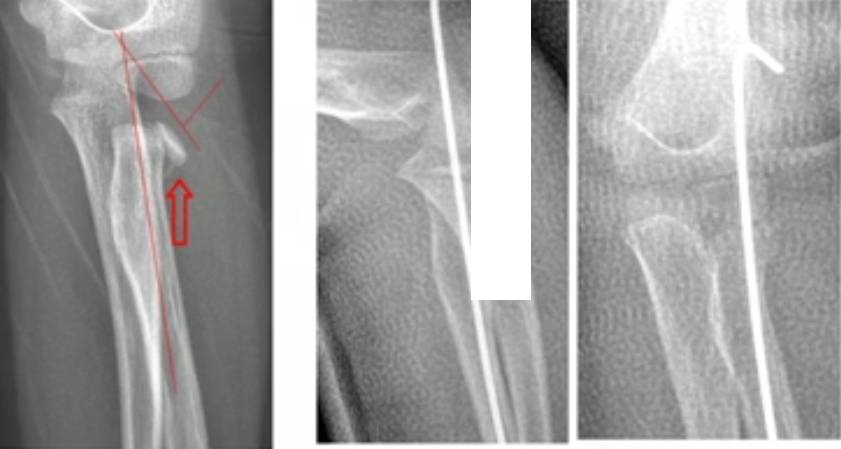

下面这是一个比较极端的例子,120 天的陈旧儿童桡骨颈骨折切开复位,同样获得满意的结果。

2 年后的 X 线片

2 年后 MRI 未发现桡骨头坏死